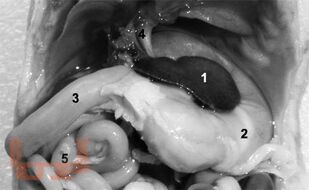

Книга посвящена актуальной проблеме биомедицины — раскрытию механизмов морфогенеза в эволюции животных, в частности, органогенеза, а также расширению существующей информации по сравнительной анатомии человека и грызунов, животных, которые часто используются в лабораторных условиях, но далеко не всегда имеют необходимый «паспорт» для правильной оценки получаемых в экспериментах результатов. Книга составлена как сборник научных очерков в виде свода оригинальных и обзорно-аналитических статей автора, опубликованных в российских научных журналах, прежде всего Российской Академии Естествознания, которые можно найти в интернете.